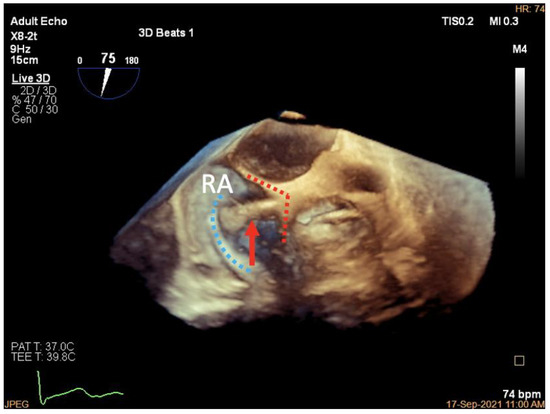

3.3. Deployment of the Tapping Screw-Shaped Anchor

3.4. Adjustment of the Clip Arm and Clamping of Annular Tissue